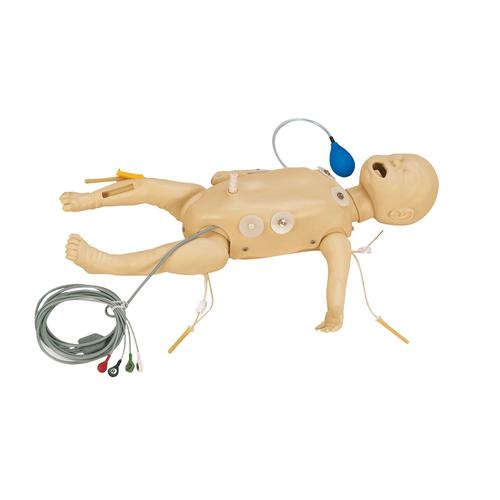

VascularAccessChild Femoral Replacement Tissue

The VascularAccessChild Femoral Replacement Tissue is an ultrasoundable soft tissue that allows users to develop their skills in complete pediatric central venous catheterization of the femoral vein.

Use ultrasound to visualize cannulation, guidewire threading, and catheter placement. Practice palpating external landmarks to identify vessel location for blind/landmark insertion approaches.

VascularAccessChild Femoral Replacement Tissue

- Anatomically correct, ultrasound compatible, femoral tissue with all relevant difficult palpating landmarks and vascular anatomy

- Market-leading durability—self-sealing tissues and veins provide value in the frequency of needle sticks and full catheterizations per access site

- Exceptional ultrasound imaging through repeated use—needle sticks and full catheterizations do not degrade the image acuity

- Red and blue simulated blood differentiate the arterial and venous vessels; provides immediate feedback on successful or unsuccessful cannulation

- Arterial pulse is present, and vein realistically compresses under palpation

- Easily adjust venous pressure regulator for vein compression or low-pressure simulation scenarios

- Replaceable tissues come pre-filled with blue venous and red arterial fluid

- Tissues can remain filled when not in use and are easy to refill with fluid when necessary